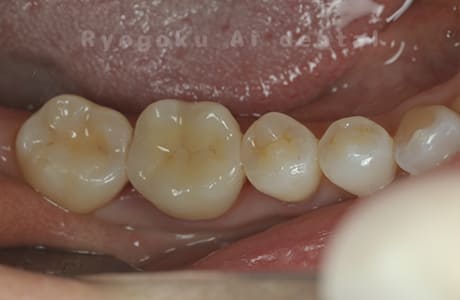

Case11

- 治療内容

- セラミッククラウン、セラミックインレー

- 治療費用

- 123,000円×2(セラミッククラン)、77,000円(セラミックインレー)

銀歯が取れて、ご来院された患者様です。奥歯2本をセラミッククラウン、手前の小臼歯をセラミックインレーで治療を行いました。